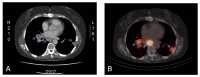

Monoclonal antibody G250 (mAbG250) recognizes a determinant on carbonic anhydrase IX (CAIX). CAIX is expressed by virtually all renal cell carcinomas of the clear cell type (ccRCC), but expression in normal tissues is restricted. The homogeneous CAIX expression in ccRCC and excellent targeting capability of mAbG250 in animal models led to the initiation of the clinical evaluation of mAbG250 in (metastatic) RCC (mRCC) patients. Clinical studies confirmed the outstanding targeting ability of mAbG250 and cG250 PET imaging, as diagnostic modality holds great promise for the future, both in detecting localized and advanced disease. Confirmation of the results obtained in the non-randomized clinical trials with unmodified cG250 is needed to substantiate the value of cG250 treatment in mRCC. cG250-Based radio immuno-therapy (RIT) holds promise for treatment of patients with small-volume disease, and adjuvant treatment with unmodified cG250 may be of value in selected cases. In the upcoming years, ongoing clinical trials should provide evidence for these assumptions. Lastly, whether cG250-based RIT can be combined with tyrosine kinase inhibitors, which constitutes the current standard treatment for mRCC, needs to be established.